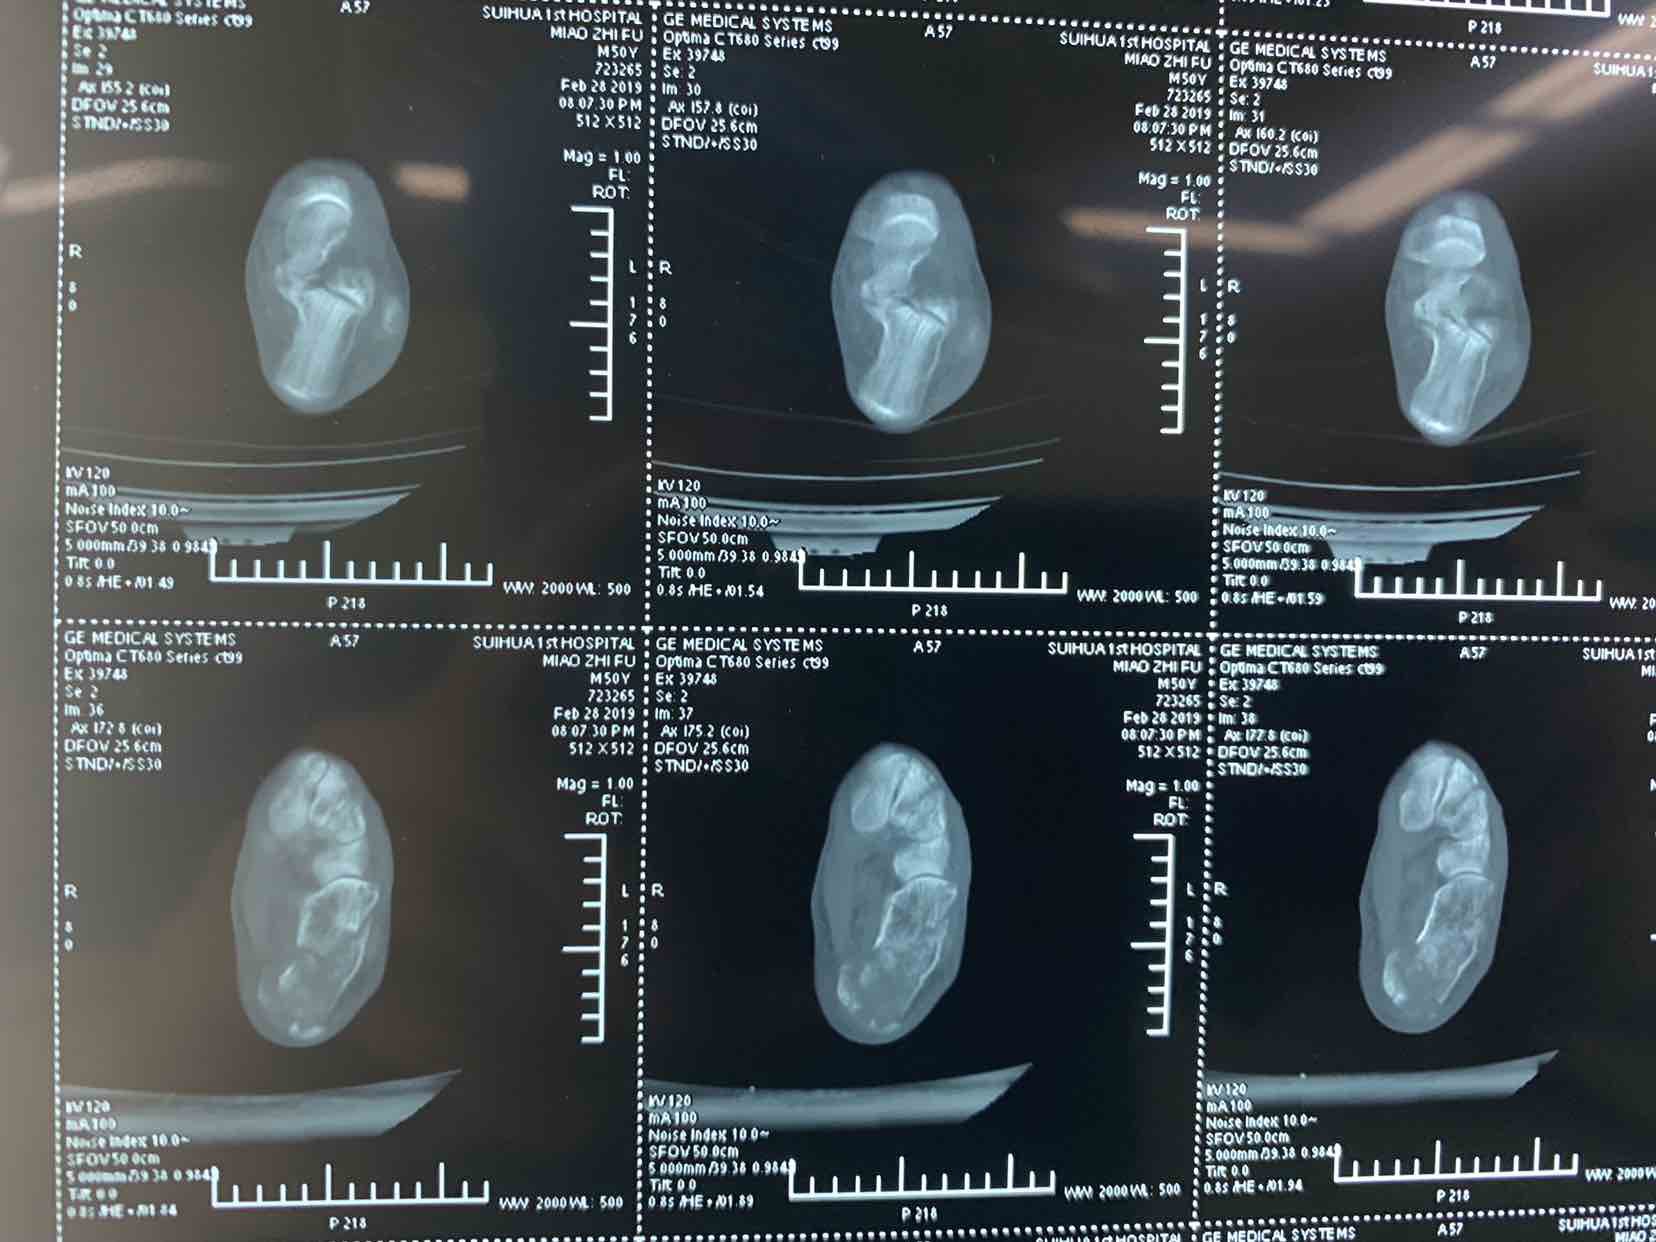

患者因自二米高处坠落,左侧足跟肿痛畸形活动受限一小时收入院。患者于一小时前不慎自二米高处坠落。当即左侧足跟肿痛。畸形。不能下地走路。急来诊。门诊拍片提示左侧跟骨骨折。门诊以左侧跟骨骨折收入院。

查体见左侧左跟局部肿胀。足弓消失。跟骨横径增宽。局部畸形。活动受限。不能下地走路。局部皮下淤血。拍片提示左侧跟骨粉碎性骨折。断端移位。